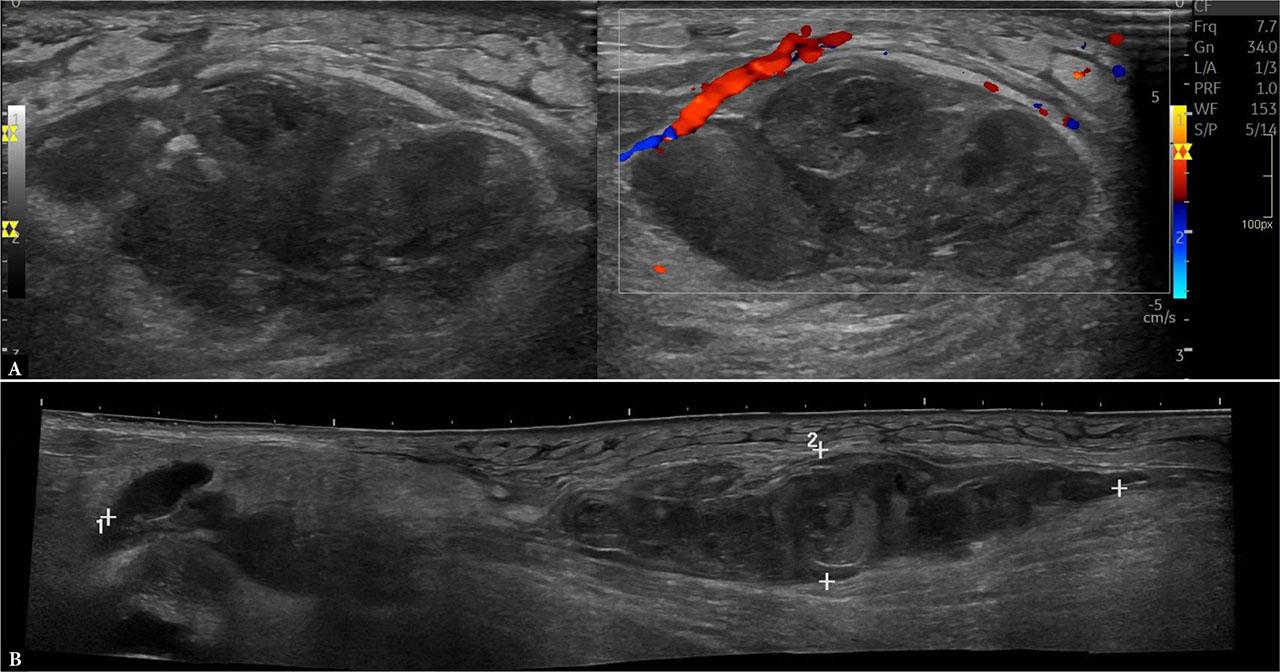

Given the high suspicion of an infectious process, a focused musculoskeletal US was performed to assess for potential abscess formation. US imaging demonstrated a large, markedly inhomogeneous lesion within the distal third of the right biceps femoris muscle, which appeared to occupy nearly the entire cross-sectional area of the muscle. The sonographic appearance was most consistent with an intramuscular abscess, particularly in the context of intravenous drug use and recent postpartum immunosuppression (Fig. 5). Further evaluation with contrast-enhanced imaging was necessary.

Ultrasound of the right thigh showing a large heterogeneous intramuscular collection within the biceps femoris muscle (4 × 5 × 10 cm), containing mixed hypoechoic and anechoic components (A) and presenting no internal vascularity on CD (B), suggestive of an intramuscular abscess

US imaging revealed a large, markedly heterogeneous subcutaneous mass with increased vascularity. In the setting of a slowly growing, newly painful subcutaneous mass in a patient on anticoagulation, differential diagnosis includes chronic hematoma; however, the echogenicity, internal calcification, and vascularity strongly favored the diagnosis of a soft tissue sarcoma (Fig. 6).

Ultrasound of the medial aspect of the right lower leg showing a large polylobulated subcutaneous mass (5.3 × 4.2 × 7.4 mm) with internal septations and a small calcification (A). CD imaging demonstrates both peripheral and internal vascularity (B), consistent with a soft-tissue sarcoma